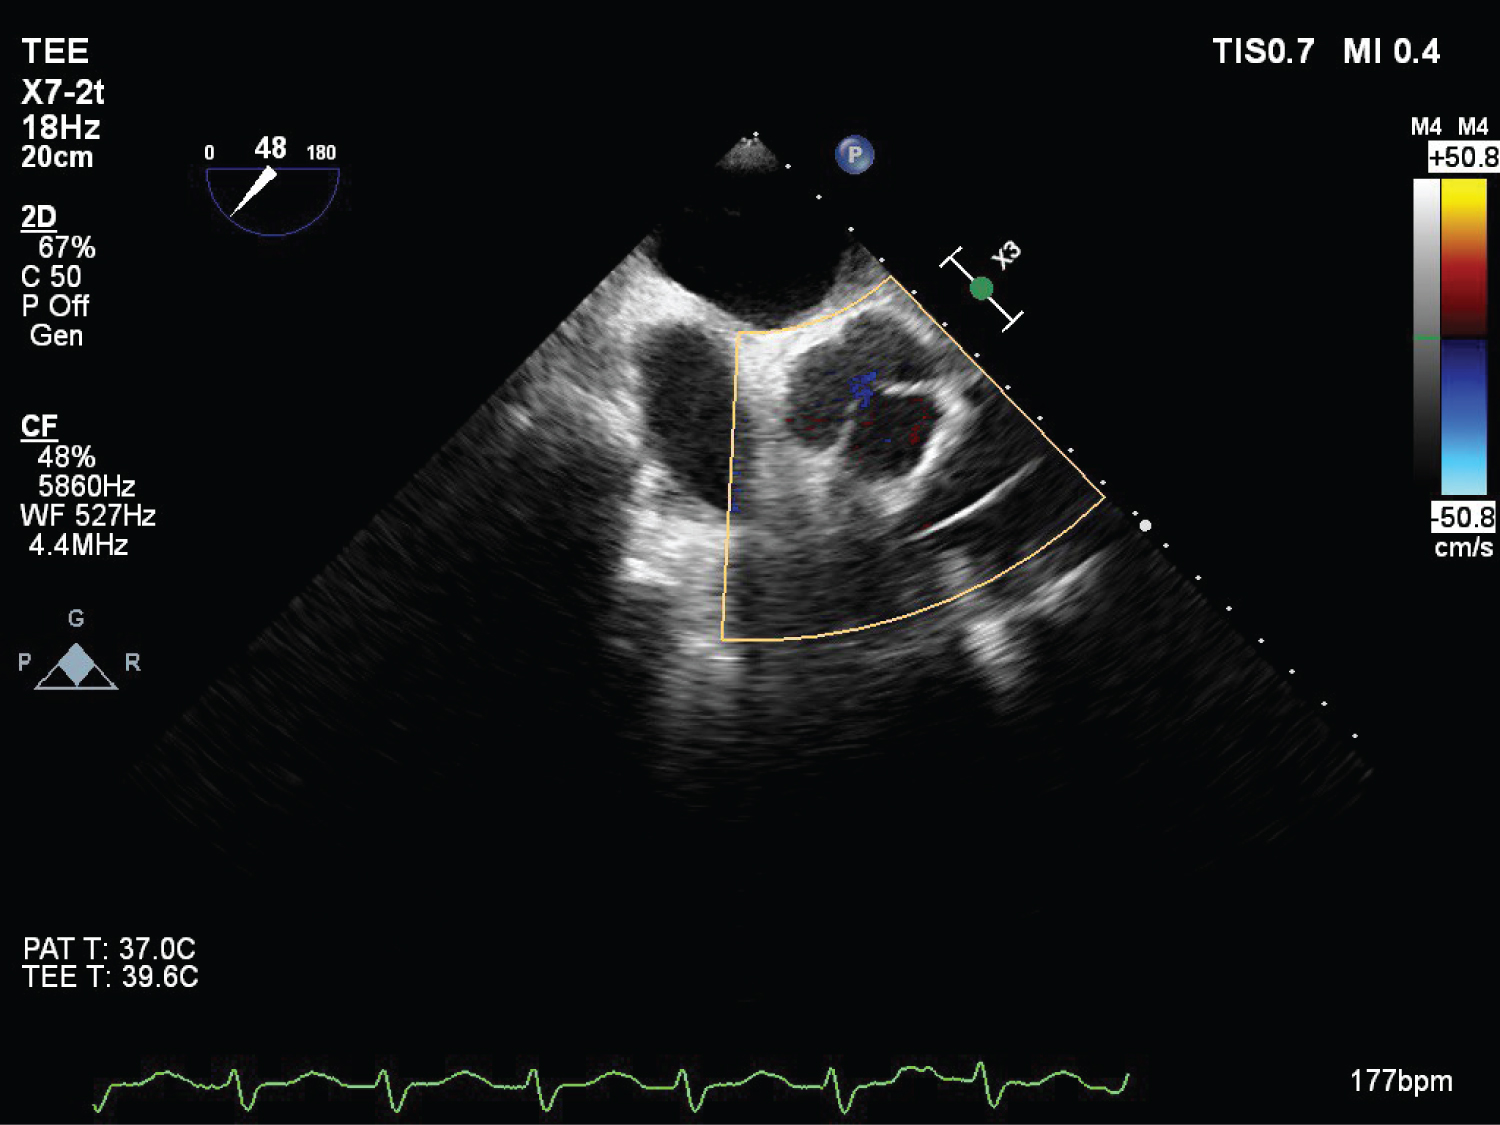

On echocardiography, aneurysmal appearance of the involved sinus and the presence of a “windsock,” protruding into the receiving chamber are characteristic of RSOV [7] (Figure 1, Figure 2, Figure 3, Figure 4 and Figure 5) ( Video 1 and Video 2 ).

Figure 3: (TEE) Mid esophageal four chamber view with colour Doppler showing blood flow across VSD (Left to right shunt). View Figure 3